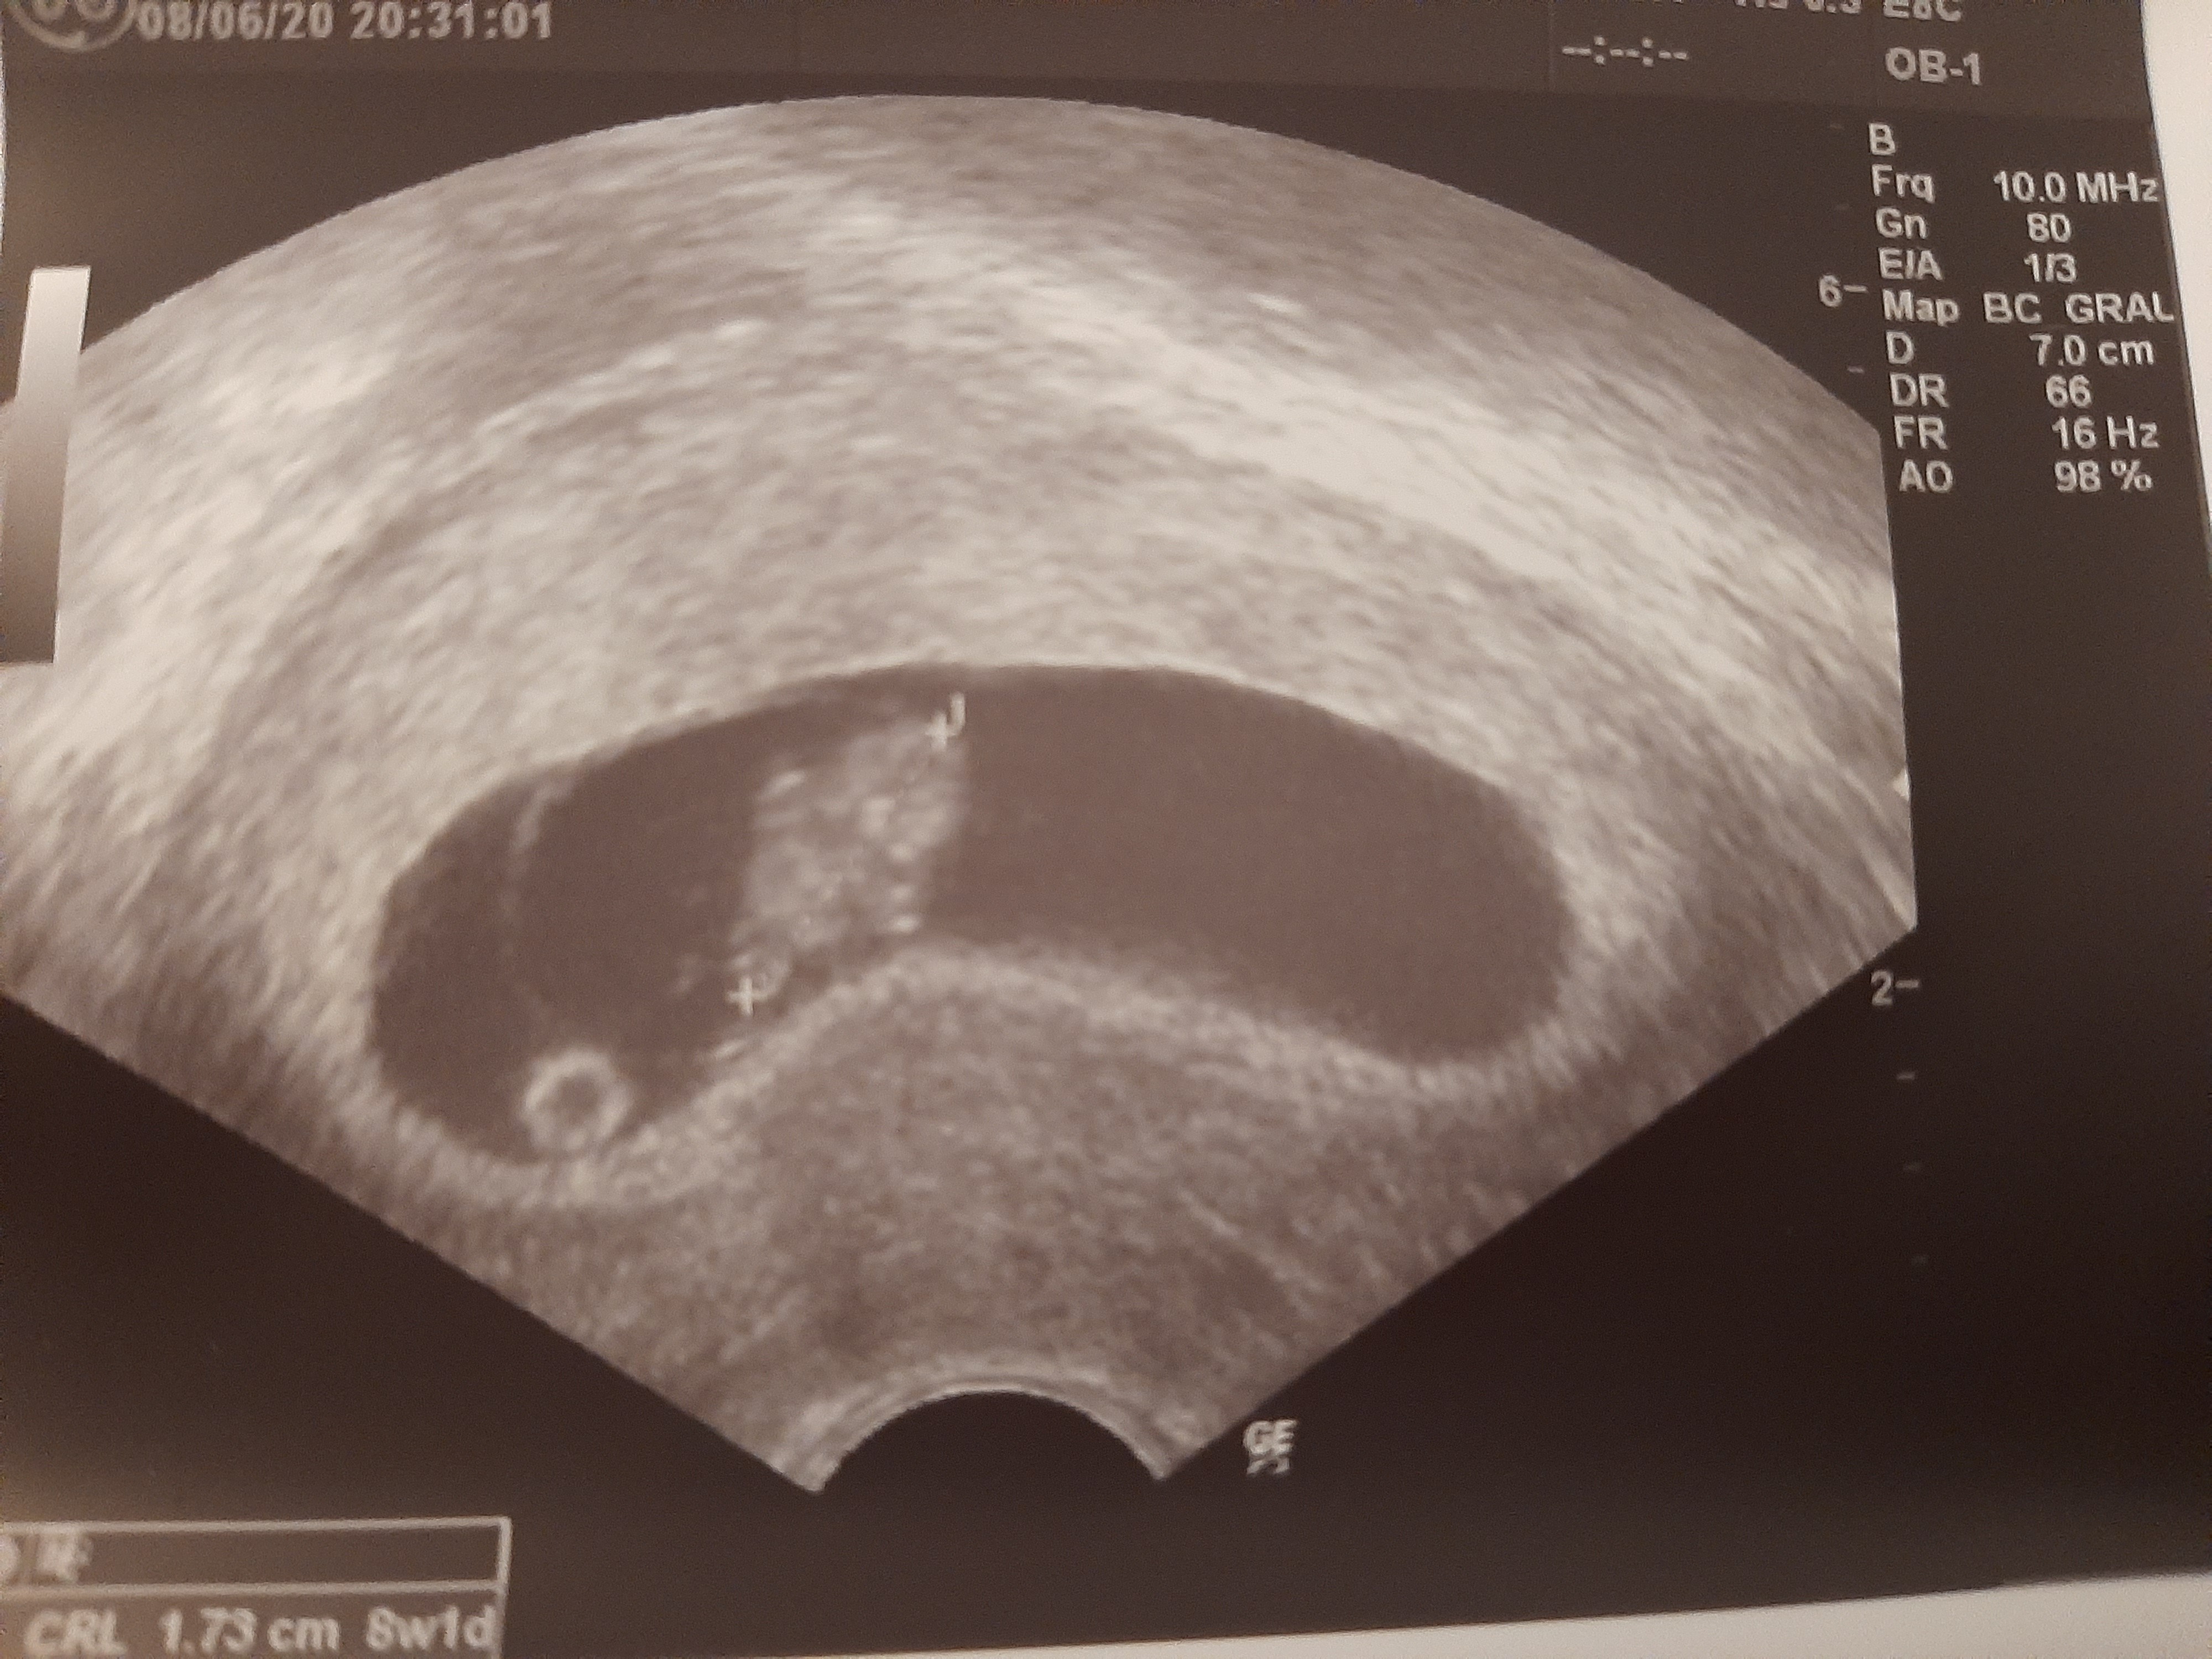

8+1 I mój śliczny kaczorek 🥰

Załączniki

• 20200608_182706.jpg

20200608_182706.jpg

1,8 MB · Wyświetleń: 103